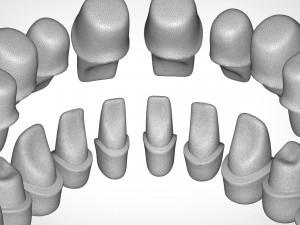

dental anatomy library with thimble crowns - azure Model do druku 3D

dental anatomy library with thimble crowns - azure. position of thimble crowns is same as teeth position. all teeth is separate files. if you want to publish or sell these files please contact me.

dental anatomy teeth tooth morphology jaw skelet exocad cad 3dprint library dentist science medicine mouth toothbrush body printable thimble crownBrak komentarzy dla tego produktu.